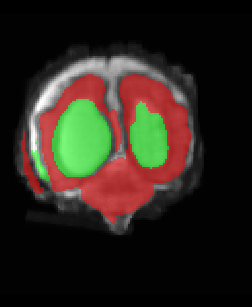

Limiting failures of machine learning systems is of paramount importance for safety-critical applications. In order to improve the robustness of machine learning systems, Distributionally Robust Optimization (DRO) has been proposed as a generalization of Empirical Risk Minimization (ERM). However, its use in deep learning has been severely restricted due to the relative inefficiency of the optimizers available for DRO in comparison to the wide-spread variants of Stochastic Gradient Descent (SGD) optimizers for ERM. We propose SGD with hardness weighted sampling, a principled and efficient optimization method for DRO in machine learning that is particularly suited in the context of deep learning. Similar to a hard example mining strategy in practice, the proposed algorithm is straightforward to implement and computationally as efficient as SGD-based optimizers used for deep learning, requiring minimal overhead computation. In contrast to typical ad hoc hard mining approaches, we prove the convergence of our DRO algorithm for over-parameterized deep learning networks with ReLU activation and a finite number of layers and parameters. Our experiments on fetal brain 3D MRI segmentation and brain tumor segmentation in MRI demonstrate the feasibility and the usefulness of our approach. Using our hardness weighted sampling for training a state-of-the-art deep learning pipeline leads to improved robustness to anatomical variabilities in automatic fetal brain 3D MRI segmentation using deep learning and to improved robustness to the image protocol variations in brain tumor segmentation. Our code is available at https://github.com/LucasFidon/HardnessWeightedSampler.